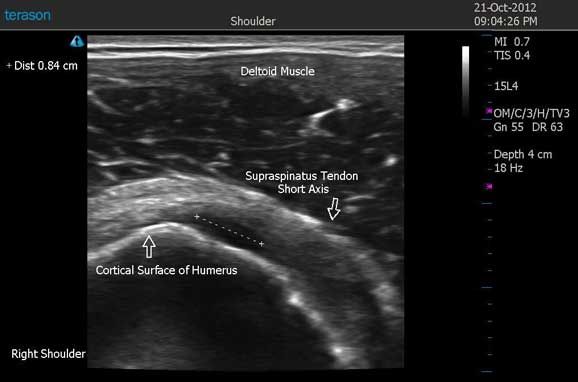

Figure 3 demonstrates a 0.84cm hypoechoic defect with loss of the normal fibrillar pattern on the articular surface of the supraspinatus tendon. Also shown, is slight irregularity of the cortical surface of the humerus on the short axis scan. On dynamic scans (not shown), there was no evidence of impingement or retraction of the supraspinatus tendon. The transducer was toggled over this hypoechoic defect on both the long and short axis to ensure this defect was indeed real.